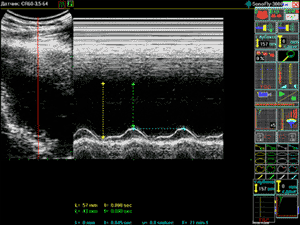

Cardiologist's Workstation SonoFly-3000 unit for ultrasonic diagnostics allows to get qualitative images of heart, its four chambers, valves in motion in the real time mode. Convenience and functionality of M and B+M modes, calculation of the main cardiac indexes are the additional reasons to choose SonoFly-3000 as a workstation for a cardiologist.

The ultrasonic examination of the heart (echocardiography) estimates the peculiarities of heat and vessels structure, chambers dimensions, its contractive function, position and diameter of vessels. It diagnosticates heart faults, failure of myocardium contraction with ischemic heart disease, myocardium hypertrophy, failure of diastolic function with arterial hypertonia, pathology of myocardium and heart membranes. The M-scanning mode is of peculiar value during cardiography. This scanning goes by one narrowly directed US-beam. SonoFly-3000 unit for ultrasonic diagnostics allows cardiography in the following modes: B, B+B, B+M and M.